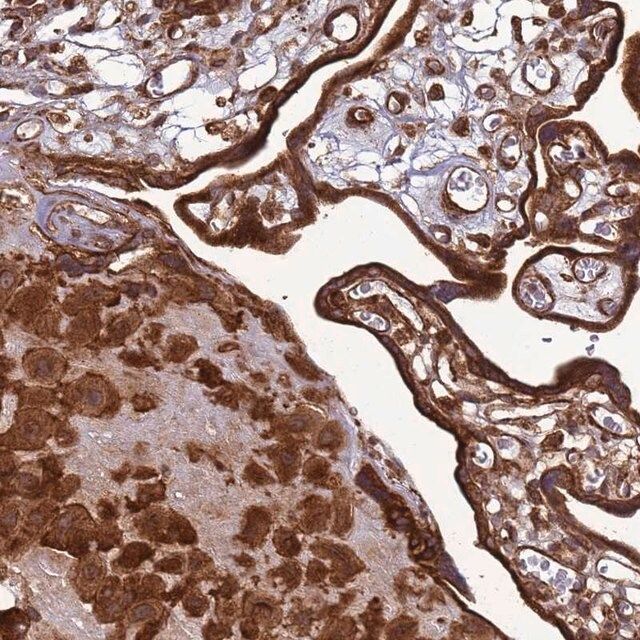

水通道蛋白 4 (aquaporin 4,AQP4) 是一种内源性蛋白,属于水通道蛋白家族,由 13 个成员组成。该基因位于人类 18 号染色体 q11-q12,有 4 个外显子和 3 个内含子。编码的蛋白有 5 个环,由 6 个跨膜结构域干预。环 A、C 和 E 面向浆外区,环 B 和 D 存在于胞浆区。在肺、胃和肾等外周器官中表达。是中枢神经系统表达的主要水通道。它由星形胶质细胞表达,并优先定位于星形胶质细胞的终足突起。它以两种可变剪接形式存在— 长的称为 M1,短的称为 M23。

人类蛋白质图谱项目可细分为三个方面的工作:人类组织图谱、癌症图谱和人类细胞图谱。支持 Tissue and Cancer Atlas 项目而产生的抗体,已经通过免疫组化针对数百个正常和疾病组织进行了测试,通过 Human Cell Atlas 项目最近的努力,很多已经通过免疫荧光法进行了表征,不仅在组织级别,现在也在亚细胞级别绘制了人类蛋白质组图谱。通过点击图像库链接,可以在 Human Protein Atlas (HPA) 位点上查看这些图像和这个庞大数据集的集合。要查看这些协议 和其他有关 Prestige 抗体和 HPA 的有用信息,请访问sigma.com/prestige。

水通道蛋白 4 (aquaporin 4,AQP4) 是脑内主要的水转运体,被认为是维持脑内水分稳态的重要物质。因此,AQP4 可能在脑水肿的发病机制中起重要角色。研究显示,这种转运体在脑缺血中过度表达。因此,它可能有潜力成为缺血性脑水肿的治疗靶点。该基因多态性与脑损伤反应和脑外伤患者的临床预后相关。AQP4 的短亚型 (M23) 有利于颗粒正交排列 (orthogonal array of particles,OAP) 的形成,OAP 的大小由短 (M23):长 (M1) 亚型的比例决定。已知这些 OAP 与视神经脊髓炎 (NMO) 中产生的致病性自身抗体相互作用。因此,对该蛋白的进一步研究可能为 NMO 的发病机制和治疗提供见解。

- 44例正常人类组织以及20例最常见癌症类型组织的IHC组织阵列。